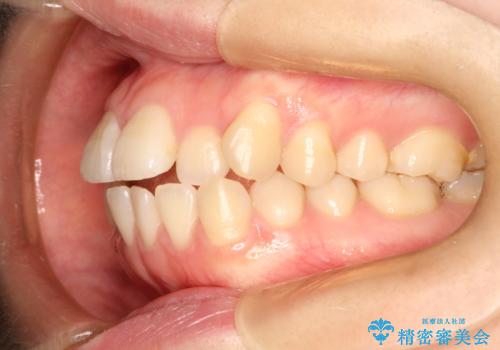

前歯にがたつきがあり、上下の歯が咬み合っていない状態でした。

歯列の横幅をひろげるのと、歯と歯の間をわずかに削ることにより、前歯のがたつきと、開咬を改善しました。